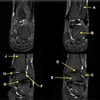

Perfectly

11

Q

What is letter A?

A

ANTERIOR LABRUM

How well did you know this?

1

Not at all

2

3

4